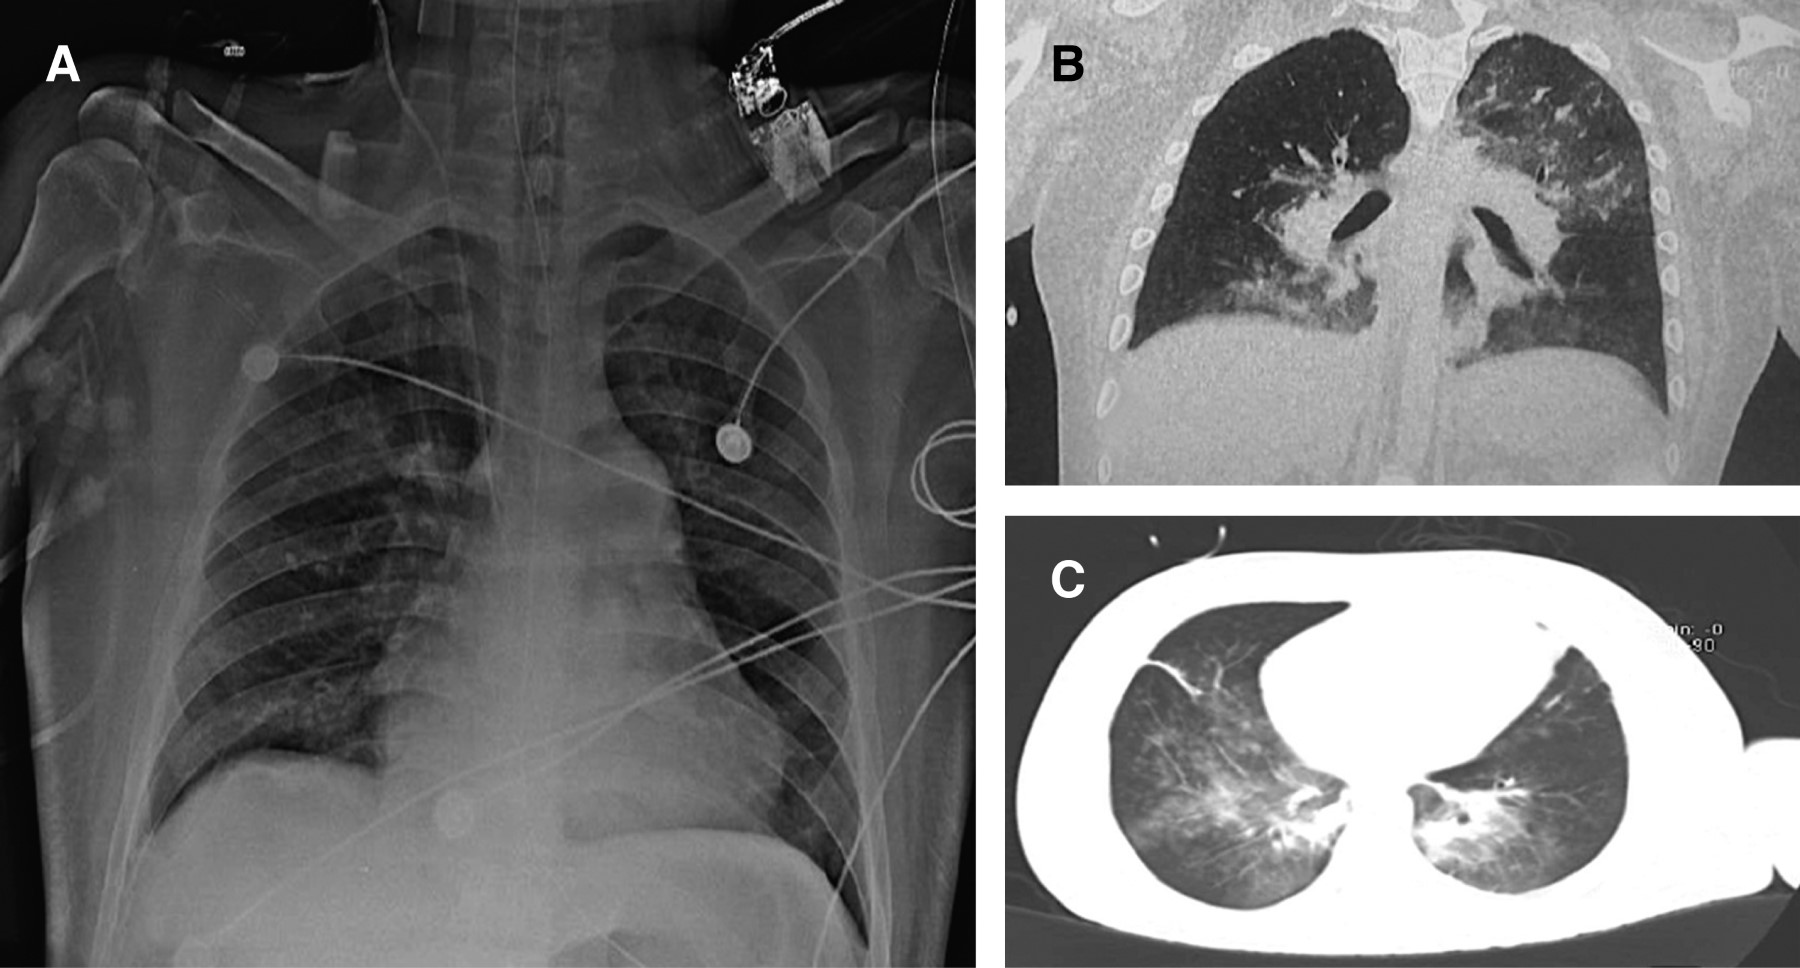

En primeras horas de hospitalización presenta hemoptisis, dolor torácico opresivo súbito, disnea de reposo, hipoxemia e hipotensión persistente, por lo que requirió ventilación mecánica invasiva y soporte vasopresor. Ultrasonido pulmonar muestra patrón B en zona 5 y 6 derechas y zonas 4, 5 y 6 izquierdas, ecocardiografía rápida evidencia asincronía en la contractilidad de las cámaras ventriculares, dilatación ventricular derecha y ventrículo izquierdo con "signo del beso". Monitoreo de gasto cardiaco con sistema USCOM (monitor multiparamétrico ECG USCOM 1A®) mostró gasto cardiaco de 3.3 L/min, índice cardiaco de 1.6 L/min/cm2, resistencias vasculares sistémicas (RVS): 1,531 ds/cm2, volumen sistólico (VS) 35 cm3. Angiotomografía de tórax con zonas en vidrio despulido hacia segmento apicoposterior, superior derecho, basal anterior izquierdo, posterobasales y basales laterales, así como áreas con aspecto algodonoso sobre los segmentos posteriores y posterobasales bilaterales en relación con hemorragia alveolar; ambos segmentos posteriores con zonas de trombosis crónica de arterias pulmonares y datos indirectos de hipertensión pulmonar e insuficiencia cardiaca derecha. Se retira anticoagulantes orales, se administra plasma fresco congelado hasta meta objetivo de INR en 2.5 y se inicia tratamiento inmunosupresor con corticoesteroides (Figuras 1 y 2).

La fibrobroncoscopia permite identificar los casos con alta sospecha cuando la hemoptisis no es evidente. En el lavado broncoalveolar se identifican macrófagos cargados de hemosiderina a partir de las 48 horas de iniciado el cuadro clínico, lo que confirma el diagnóstico; no obstante, hay que considerar que éstos también pueden presentarse en casos de procesos infecciosos (citomegalovirus, Legionella e incluso Candida albicans), o exacerbaciones de enfermedades pulmonares intersticiales. Los estudios radiográficos, particularmente los de alta resolución, aportan información clave para el diagnóstico (tomografía computada de tórax), la radiografía simple de tórax puede mostrar hallazgos atípicos con áreas focales asimétricas bilaterales de consolidación u opacidades en vidrio deslustrado; las radiografías de tórax de los pacientes con lupus y hemorragia alveolar difusa también pueden tener una apariencia normal o casi normal (nótese la Figura 1 que muestra la radiografía de tórax del caso descrito).